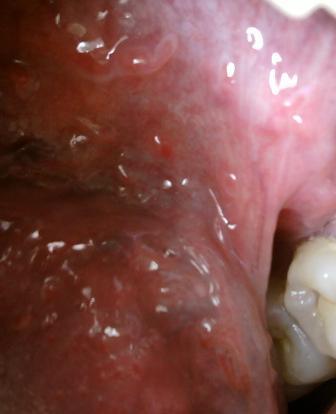

石家庄九州皮肤病医院 > 尖锐湿疣 > > > 孕妇尖锐湿疣如何选择治疗方法现在尖锐湿疣性病是比较多发的,年轻的男女是尖锐湿疣性病多发人群,但是孕妇是尖锐湿疣性病特殊人群,所以患病之后希望大家应该引起重视,及时就诊对于广大患者朋友们来说很关键。

孕妇尖锐湿疣如何选择治疗方法当确诊自己患病之后,应该及时去正规专业的医院进行诊治。专家表示:孕妇患上尖锐湿疣一般有以下几种情况:第一种情况是在怀孕之前就已经感染病毒的,第二种情况是在怀孕之后感染病毒的,这是因为感染上尖锐湿疣病毒之后并不会立即发病,而是有一段时间的潜伏期,一般是三个月左右的时间。但是不管是因为哪一种情况,患病之后都应该及时就诊。